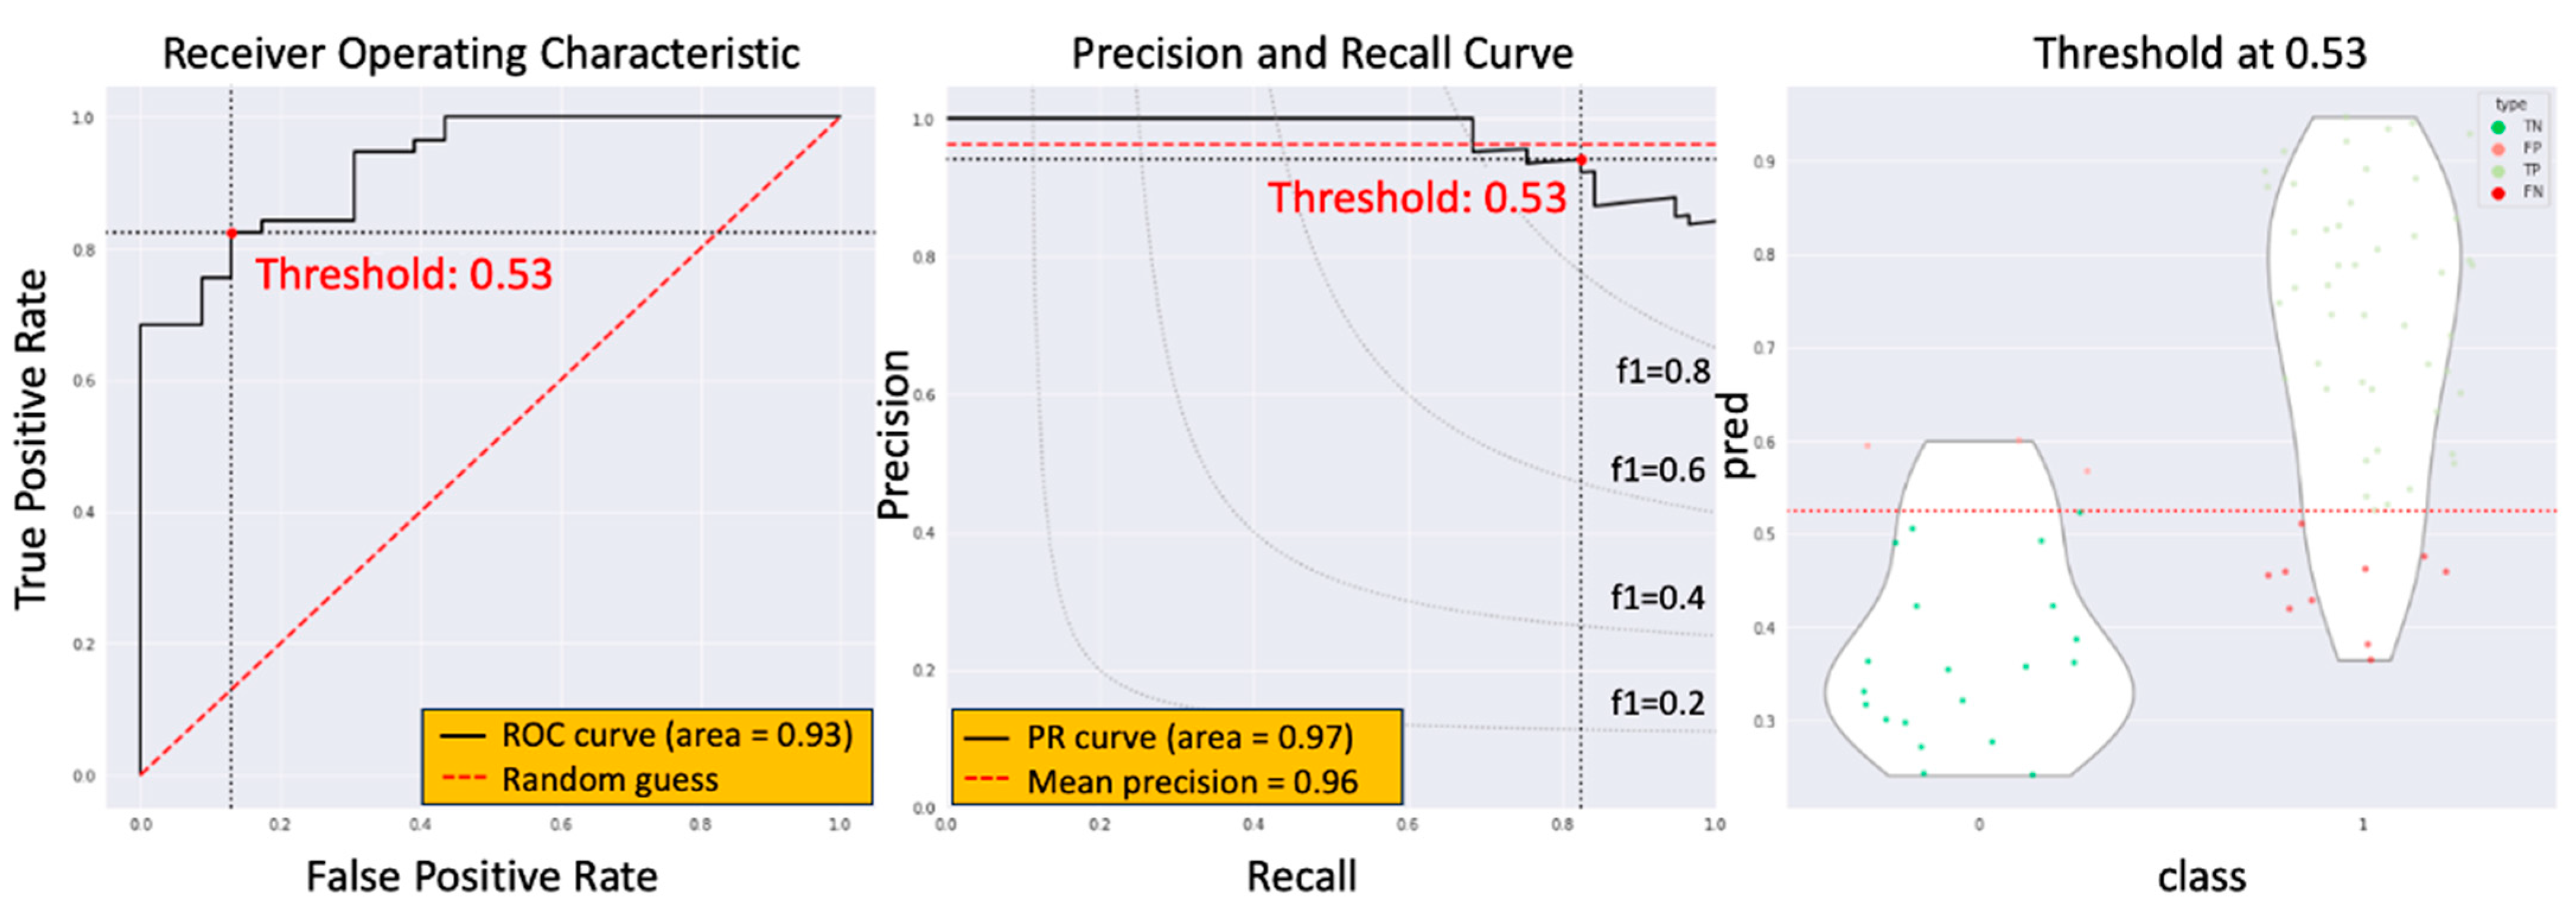

3.3. The Model Performance of DCRNet in Pathological Results